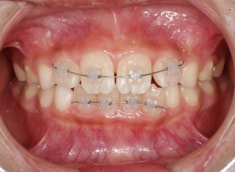

治療法:拡大プレート+フルパッシブブラケット(クリアスナップ)

治療後(8ヶ月後)

治療中